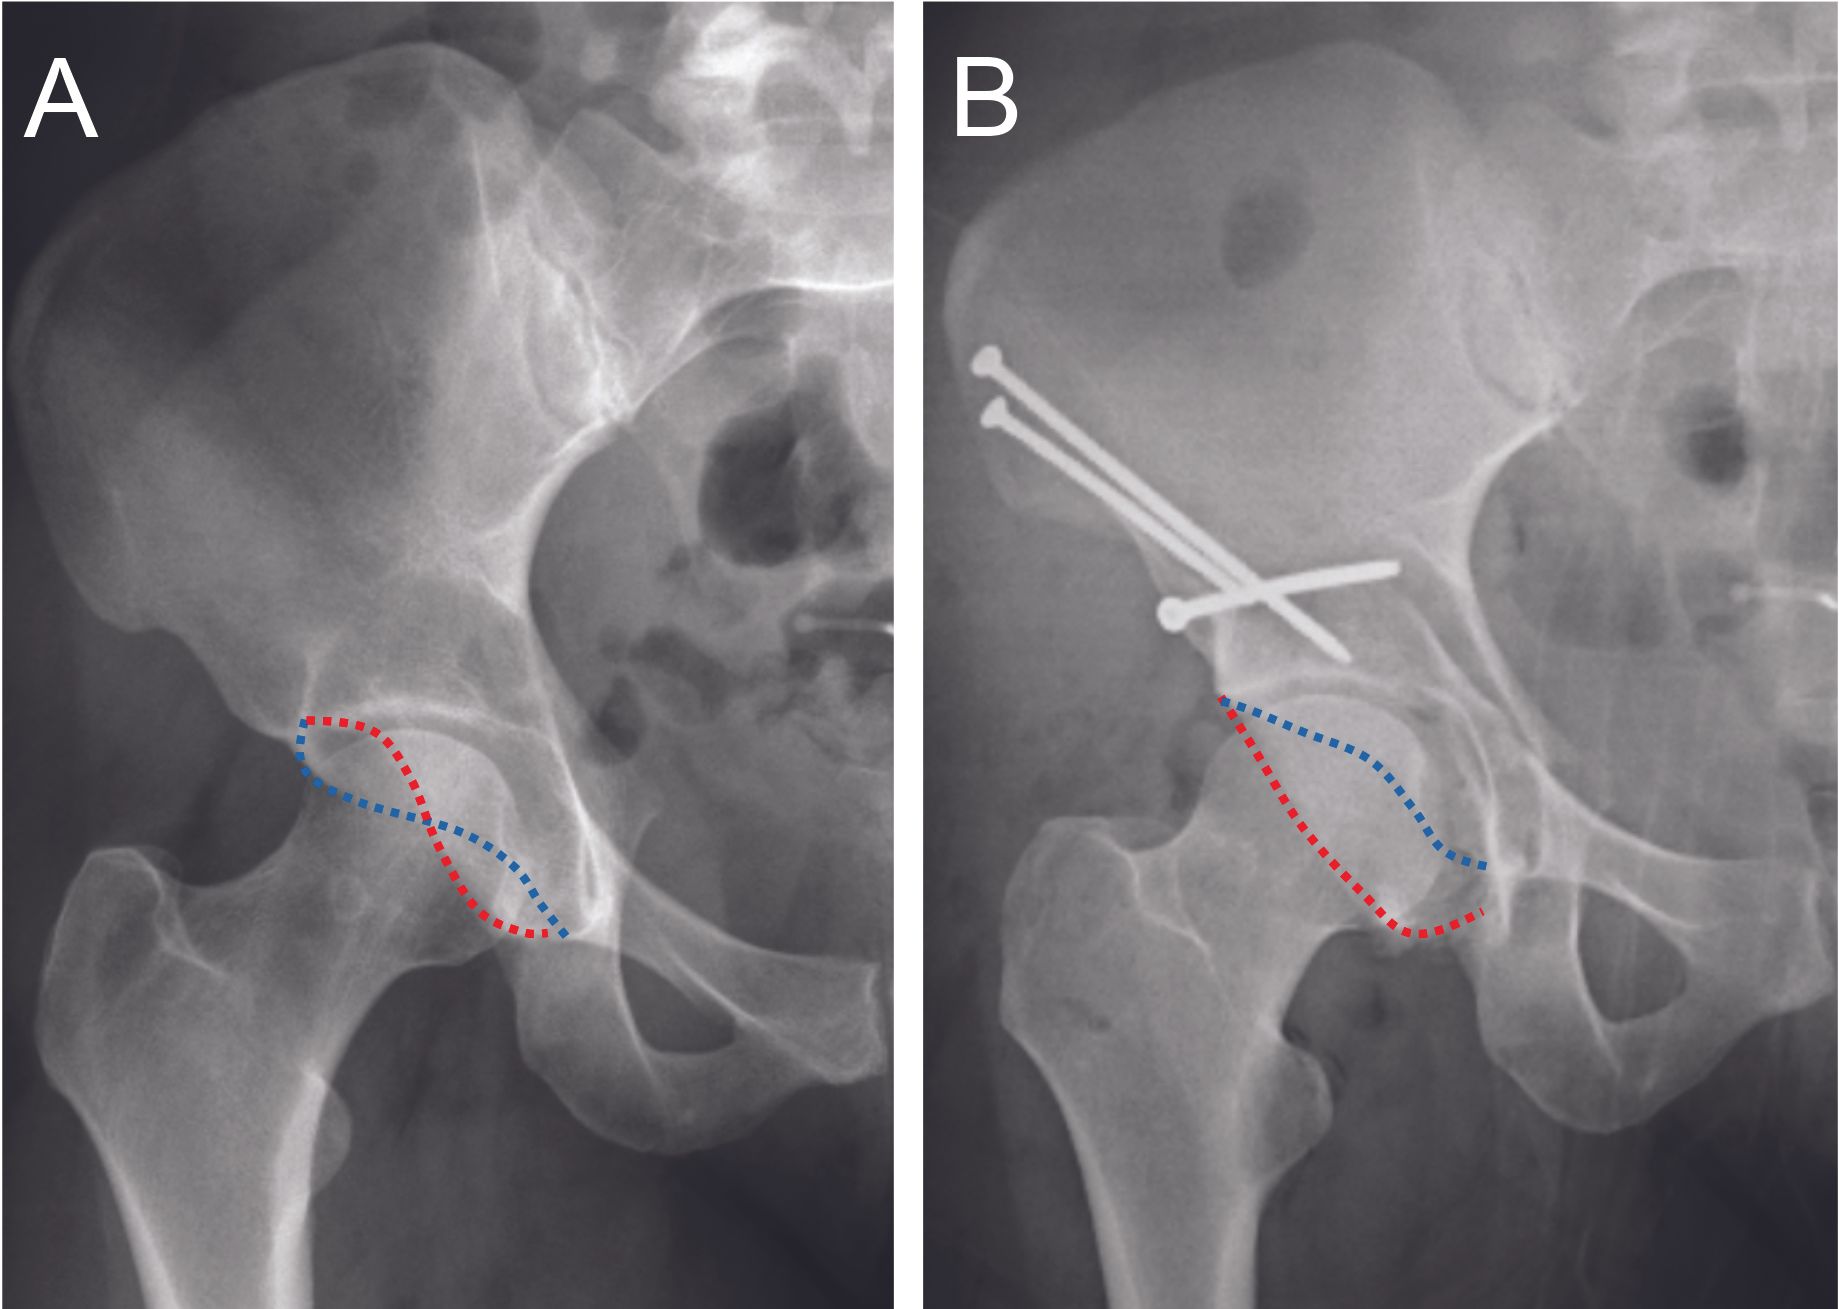

The periacetabular osteotomy (PAO) was initially described to treat dysplasia, and then the anteversion periacetabular osteotomy (19) was described to treat retroversion of the acetabulum that can lead to FAI (Figure 14).

The surgery is performed using a modified anterior Smith-Petersen approach. The principle is based on several osteotomy cuts, at the level of the ischium, the superior branch of the pubis, the supra-acetabular region and the retroacetabular region, while keeping the posterior column in continuity. Mobilization of the fragment comprising the acetabulum allows reorientation and thus correction of the version of the acetabulum. This fragment is then stabilized with screws.

This is a more extensive surgery, reserved for young patients under 40 years of age (20) in cases of global retroversion of the acetabulum with a retroversion >30% (Figure 15).

In the case of associated cam impingement, it is common to combine this with a procedure on the femur, either arthroscopically or by minimally invasive anterior approach. While short-term results seem promising, few studies have shown long-term results. Peters' 2011 study (21) proposed a decision algorithm between anteversion PAO or surgical hip dislocation for correction of acetabular retroversion. Anteversion PAO would be indicated in cases of acetabular retroversion with insufficient posterior and/or lateral coverage, associated with intact hyaline cartilage. A surgical hip dislocation with resection of the anterior part of the acetabulum would be indicated in cases of acetabular retroversion with excessive anterior coverage but sufficient posterior coverage. A recent study by Zurmühle in 2017 (22) showed a higher 10-year survival rate with PAO (86%) than with acetabular resection by surgical hip dislocation (23%) in cases of acetabular retroversion resulting in FAI. The failure is probably caused by the decreased surface area in case of retroversion with anterior wall resection, resulting in hip dysplasia and thus an increased risk of coxarthrosis (23).